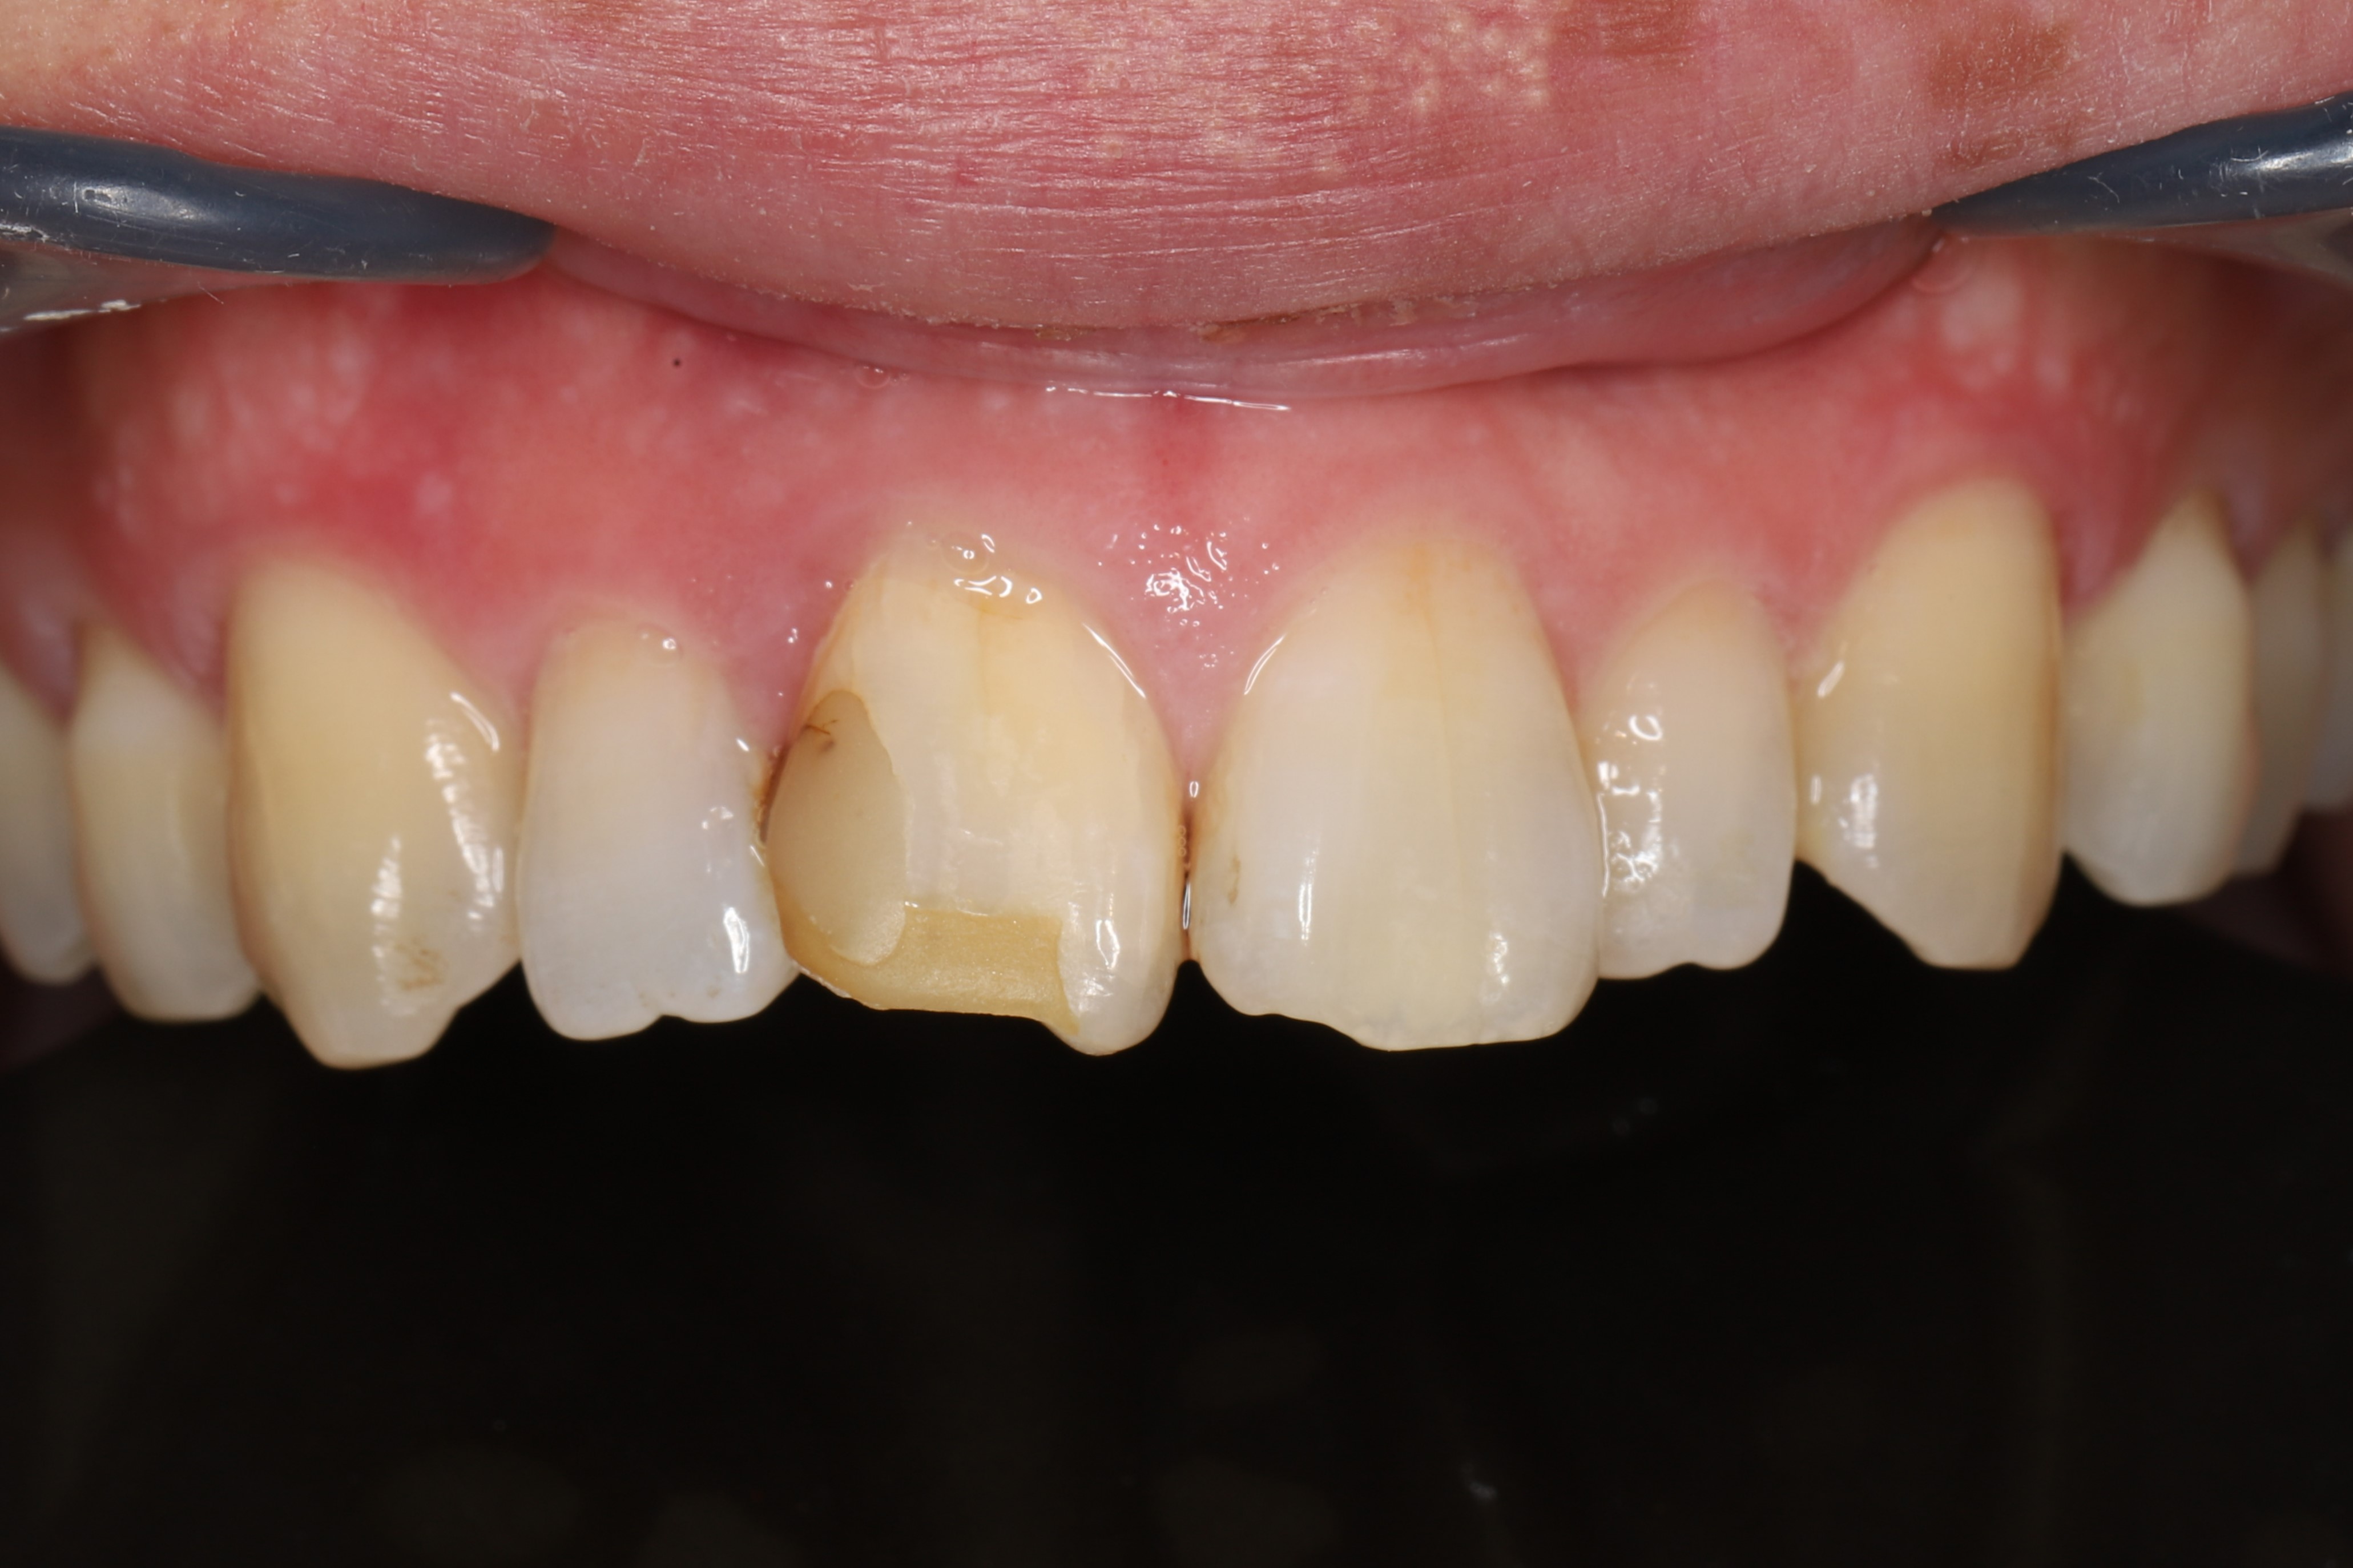

症例2(歯の色+形に問題がある場合)

ホワイトニング後(治療期間2ヶ月)

虫歯を除去し、最小限の切削量で被せ物により歯の形を改善後